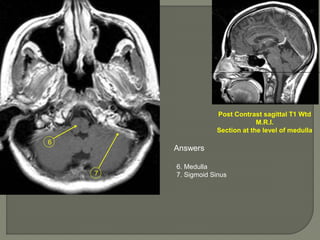

Post Contrast sagittal T1 Wtd

M.R.I.

Section at the level of medulla

Answers

6. Medulla

7. Sigmoid Sinus